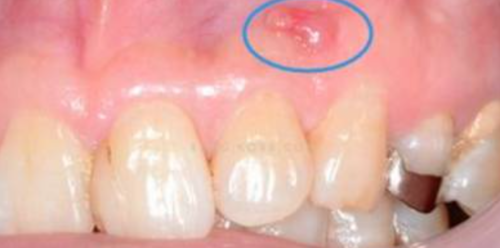

正常情况下拔牙术后疼痛适的通常3-7天消失,3个月左右拔牙窝内会长出新的骨质形成骨性愈合。而在双膦酸盐的药物影响下,牙槽骨的改建受到干扰,无法正常的完成破骨-新骨形成的过程,从而导致拔牙创经久不愈并继发感染,最终演变为颌骨骨坏死,甚至有使用过双膦酸盐药物的患者,在没有进行拔牙手术的情况下,仍然因为牙齿的发炎诱发颌骨骨坏死,这都给病人造成长期的痛苦及严重心理的负担。

目前或之前有使用BP;颌骨外露持续8周以上;颌骨没有接受过放射线治疗。

临床分为3期:Ⅰ期有死骨出现但无明显临床症状;Ⅱ期病变局限在牙槽骨内,死骨暴露,并有红肿疼痛等感染症状,伴或不伴口内瘘管;Ⅲ期病变超出牙槽骨范围出现死骨,伴疼痛、感染,并至少伴有病理性骨折、口外瘘管、下颌骨下缘或鼻窦底部骨质溶解破坏3 项之一。